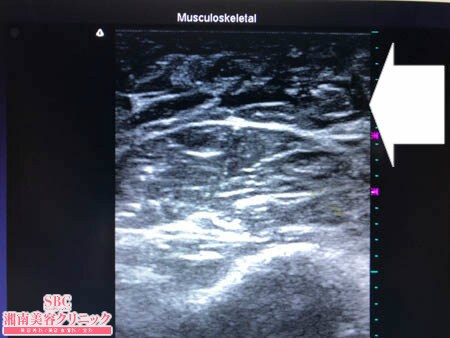

No.205740【脂肪吸引】【動画あり】湘南美容外科脂肪吸引最高責任者である竹田先生による脂肪吸引のフォトギャラリー!スタッフさんからの手術のご依頼は何よりも信頼の証!太ももの脂肪吸引に大満足して今度は二の腕を細くする!術中3Dタッチビュー・左ちからこぶ

患者様の皮下脂肪の質は

かなり線維質で硬く

脂肪吸引がしにくい状態でした。

しかしそれは前回の

太ももの脂肪吸引の際に

わかっていたことですので

それを踏まえて手術に臨みましたから

しっかりと結果を出すことができています。